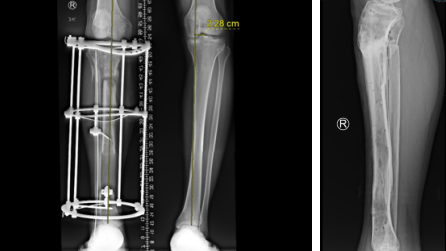

小张一场意外车祸导致小腿胫骨粉碎性骨折,在仁慈医院进行了骨延长手术,得知曹广超主任来看望他后,早早来到门口等待。

“当时医院都要截肢了,多亏转到了仁慈,保住了这条腿,现在好的很,开车带孩子去云南玩,这要截肢了哪敢想。”

胫骨粉碎性骨折,伴有腓总神经损伤

骨延长术后